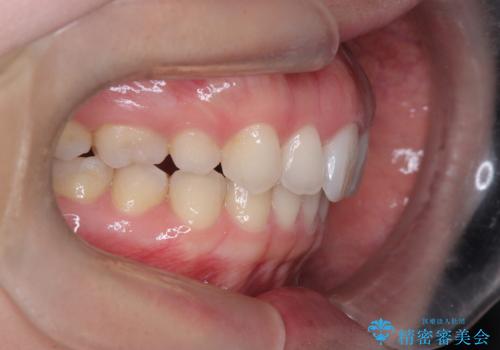

- 患者様は、上下顎の歯列不正と前歯部の突出感を主訴としてご来院されました。診断の結果、上顎左右第一小臼歯を抜歯することでスペースを確保し、歯列全体を整える方針としました。本来はワイヤー矯正が推奨されるケースですが、患者様のご希望により、透明なマウスピース型矯正装置「インビザライン」を使用した治療計画を立案しました。治療期間は約3年で、奥歯の噛み合わせを維持しながら、徐々に前歯の位置を整えました。

インビザラインは見た目の目立ちにくさと取り外しが可能な点がメリットですが、複雑なケースでは治療計画の精密さが求められます。本症例では奥歯の噛み合わせが崩れないよう注意を払いながら、マウスピースの交換タイミングを細かく設定しました。患者様には装着時間を守っていただくことが重要で、1日20時間以上の装着が必須です。また、抜歯部位のスペースを閉じる過程で、歯の動きが停滞しやすい時期もあるため、定期的なチェックを通じて治療が順調に進むよう管理しました。